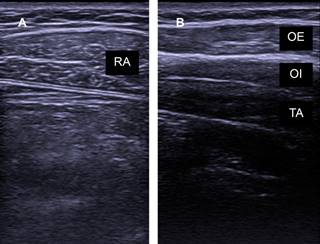

Los músculos espiratorios se encuentran en la pared abdominal, conformados por el transverso del abdomen, oblicuo interno y externo, además del recto abdominal (Figura 1). De manera secundaria puede haber participación de algunos músculos de la caja torácica.

Figura 1: Ecografía muscular de la pared abdominal. A) Músculo recto abdominal (RA). B) Músculos: oblicuo externo (OE), oblicuo interno (OI) y transverso del abdomen (TA).